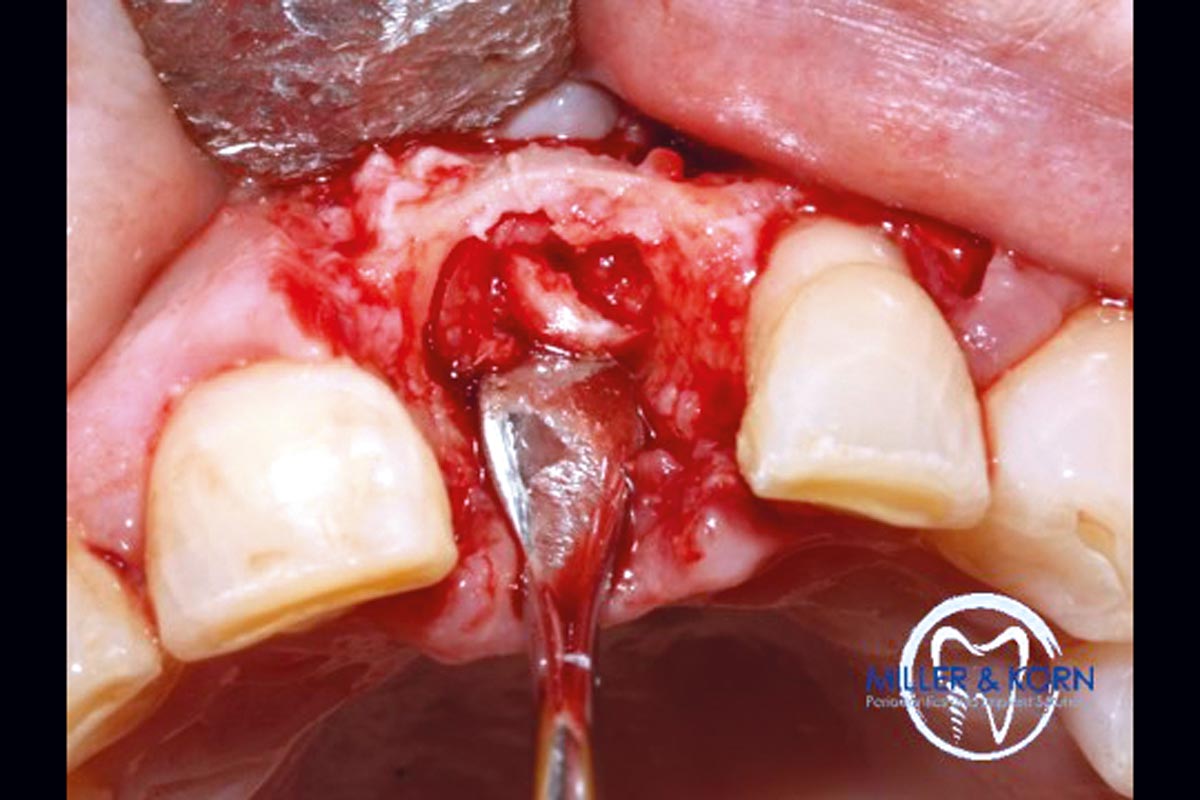

04/39 - Preparation of a full thickness flap and careful debridementImmediate implant placement and correction of horizontal and vertical bone loss using an allograft bone ring, cerabone® and Jason® membrane - Drs. Miller and Korn